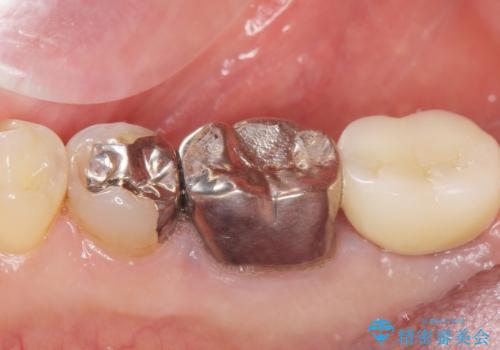

自然な見た目と咬み心地にご満足頂けました。

他院では難しいと言われていたインプラント治療が可能になり、喜んで下さいました。

インプラントの種類:スプライン ツイスト (HAコーティング)

固定様式:セメント固定

クラウンの種類:オールセラミッククラウン スタンダード